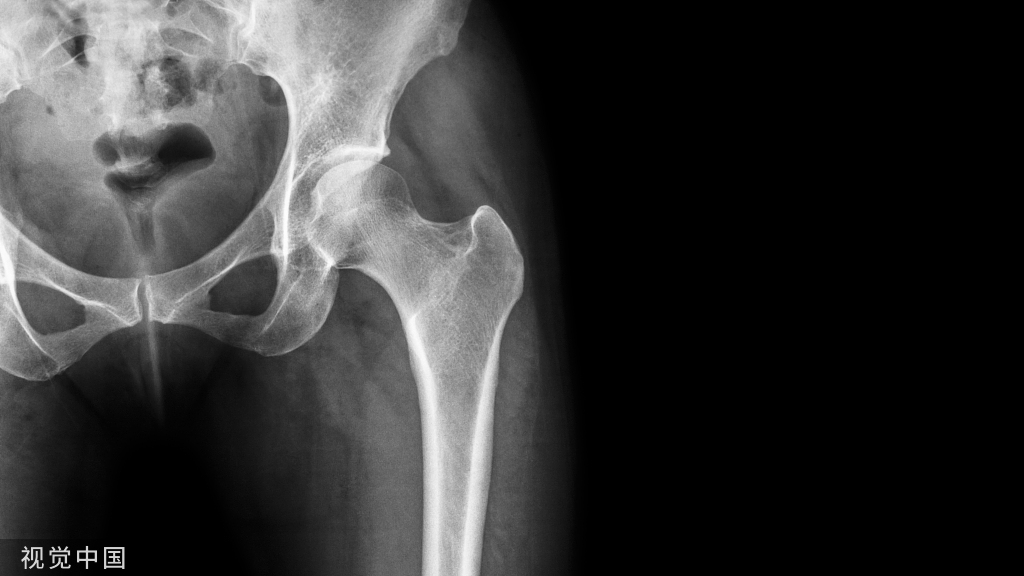

粗隆间骨折好发于老龄患者,为三大骨质疏松性骨折之一,通常需采用内固定治疗。粗隆间骨折内固定的选择,与骨折类型密切相关。关于小转子及内侧壁的重要性,已经越来越受到重视,部分内固定的失效也与其相关。有学者研究了粗隆间骨折累及小转子及内侧壁的大小与内固定失效的关系,结果发表在Injury期刊上。

介绍股骨粗隆间骨折内侧壁骨块的分类,并探讨固定后植入失败的潜在术前预测因素。

I型:小转子撕脱骨折;骨折线不超过小转子基底部;

II型:小转子基底部附近累及后内侧皮质;骨折线未达到后壁中线;

III型:累及后内侧皮质;骨折线达到或超过后壁中线。